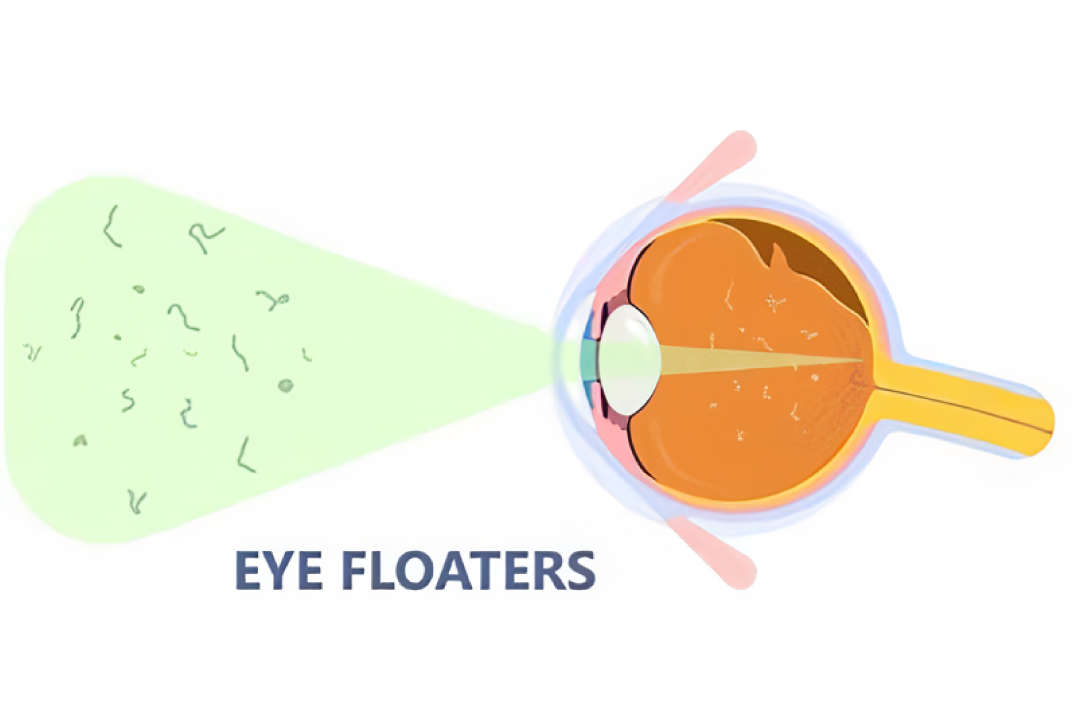

飞蚊症

玻璃体混浊,表现为眼前出现蚊蝇、云雾状黑影飘动,严重时视物模糊。其成因可归为三类:一是葡萄膜、视网膜或后巩膜炎症;二是玻璃体变性,如老年人或高度近视患者的玻璃体退行性改变及遗传性玻璃体视网膜病变;三是玻璃体先天异常。

中医认为,根据五轮学说,瞳仁属肾,肾主水,故称“水轮”。现代医学的眼底病和玻璃体混浊,在中医看来,均属瞳仁内部疾患。“肝开窍于目”、“肝和则目能辨五色”表明肝肾与眼关系密切,故滋补肝肾法对于玻璃体混浊疗效显著。睛内神膏由肾精气化生,目为肝窍,神膏混浊乃肾虚肝血不足所致。肾藏精,肝藏血,肝肾不足则清窍失养,导致玻璃体混浊等疾病。中医对玻璃体变性病变的干预具有一定疗效。

简单来说,玻璃体混浊可能由眼部炎症、玻璃体自身病变或先天异常引起,导致眼前出现黑影或视物模糊。中医认为此病与肝肾功能失调相关,可通过滋补肝肾疗法,对玻璃体变性也有一定疗效。